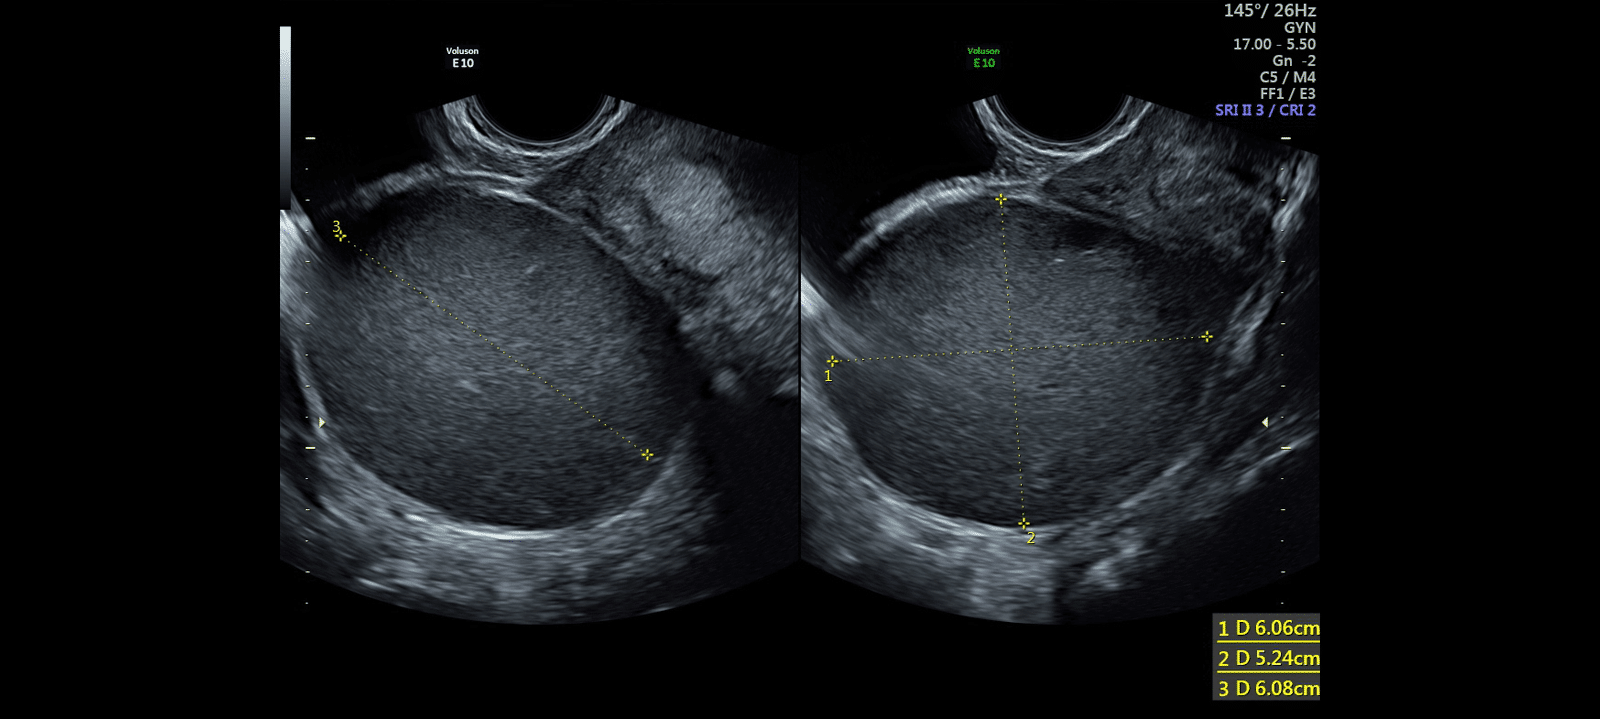

In cases of mild endometriosis, there may be nothing to see on an ultrasound, but as the disease causes more scarring and distortion, we see it more clearly on ultrasound. While it is a relatively simple thing to see endometriotic cysts in the ovaries, deeper deposits of endometriosis on the bowel or bladder are difficult to see so we use a light enema as preparation for these scans.

The value of the examination is in allowing the patient and her surgeon to be better prepared for the surgical challenges associated with deep infiltrating endometriosis of the bowel and Pouch of Douglas, if the disease is recognised pre-operatively.

While longer than a typical pelvic ultrasound, it is in other respects very similar and is done with a combination of transabdominal and transvaginal scanning.